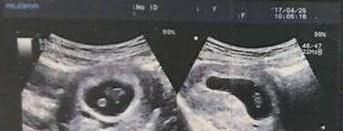

06、方法六:看B超孕囊的形状在怀孕6周到8周准妈妈要进行第一次B超,以确定是否宫内好孕以及孕周。而孕囊的形状则被很多准妈们用来判断宝宝的性别,通常的说法是,如果孕囊是茄子状,或孕囊数据有一个是另外两个的两倍,那么就是男宝宝,如果孕囊是圆形,孕囊的三个数剧呈列比,那么就是女宝宝。这一条,我的两个宝贝都符合,但是根据其他宝妈们的反馈,也有例外的。